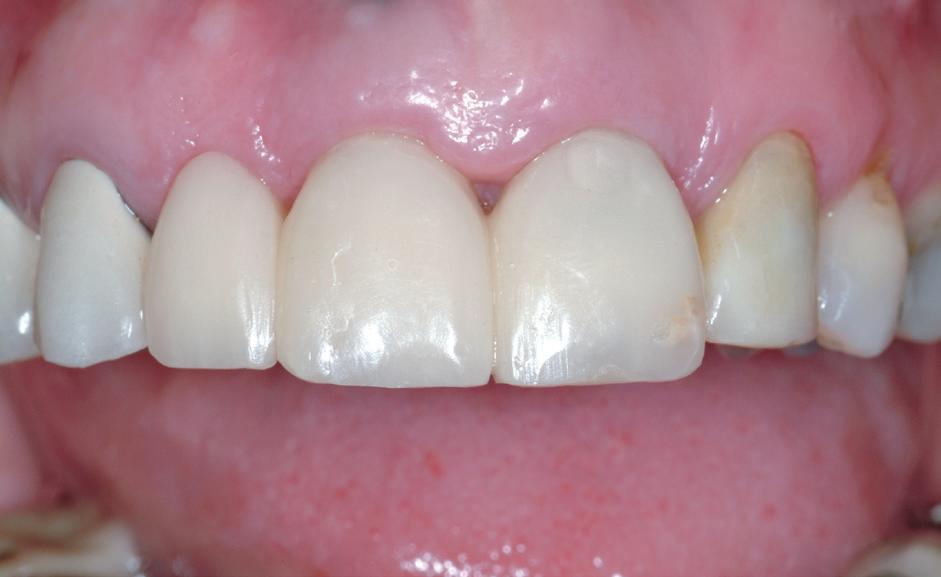

La controlul de două luni, nu au fost raportate simptome, nu s-a obiectivat radiologic nicio leziune periapicală, iar examenul clinic a

demonstrat o vitalitate în limite normale (fig. 9-10). Prin urmare, s-a decis efectuarea restaurării definitive, păstrând Biodentine™ ca bază definitivă.

Materialul Biodentine™ a fost parțial îndepărtat și peste acesta s-a plasat o obturație din compozit (fig. 11). S-a efectuat o gravare selectivă a smalțului, urmată de aplicarea unui sistem adeziv (Palfique Bond®, Tokuyama) (fig. 12-13). După foto-

polimerizare, s-a fixat sistemul de matrice (SeptoMatrix, Septodont) și s-a utilizat o matrice mare cu un inel moale pentru un contur mai bun și un punct de contact proximal (fig. 14). Restaurarea a fost începută în porțiunea distală, transformând cavitatea de clasa a II-a într-o cavitate de clasa I (fig. 15). În final, suprafața ocluzală a fost restaurată folosind compozitul Palfique LX5® (Tokuyama) (fig. 16). După fotopolimerizare, s-a aplicat gel de glicerină pentru a permite o mai bună fotoactivare a stratului superficial. Restaurarea a fost apoi finisată și lustruită, înainte de îndepărtarea digii de cauciuc și verificarea ocluziei (fig. 17).

Figurile:

10. Restaurarea Biodentine™ după 2 luni.

16. Restaurarea imediat după finalizare.

17. Situația clinică după finisare și lustruire.